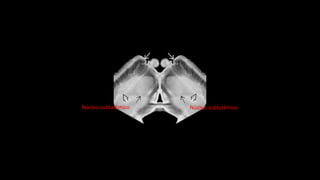

Doença de Parkinson

• Doença neurodegenerativa multissistêmica

• Parkinsonismo: Tremores, bradicinesia e rigidez

• 75% Doença de Parkinson

• Parkinson + demência = Demência da doença de Parkinson

• Parkinson + outros = Parkinson Plus

• Clínica

• Desordem neurodegenerativa

• Histopatologia

• Doença de corpos de Lewy

• Imunohistoquímica

• Sinucleinopatia

Introdução

• Etiologia

• Degeneração de neurônios dopaminérgicos (60%)

• Redução da dopamina no corpo estriado (80%)

• Idade

• Genética

• Patologia

• Atrofia mesencéfalo, com formato em “borboleta”

• Despigmentação da substância nigra

• Presença de corpúsculos de Lewy

• Tratamento

• Levodopa

• Sistema de estimulação cerebral profundo (DBS) no núcleo subtalâmico